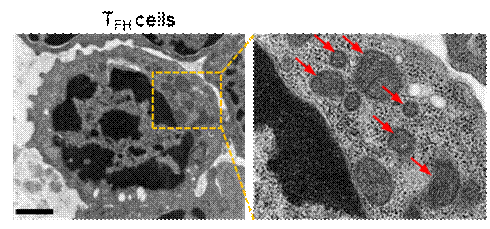

图2. 透射电镜下看到TFH细胞内皱缩和损伤的线粒体,显出铁死亡特征 (图片来源于Nature Immunology) |

2017年团队初步发现人群补硒可特异性激活TFH细胞功能,而对其他T细胞亚群无显著性影响。这个有趣的现象提示研究者,硒与TFH细胞亚群存在某种神秘的关联,可能是解密硒调控免疫功能的突破点。研究者进一步发现,TFH细胞存在一种不同于其他T细胞亚群的新型死亡方式-铁死亡(ferroptosis),TCR和PD-1/L1共刺激信号是诱发TFH细胞内脂质ROS水平显著上升、从而发生铁死亡的关键因素。研究证实,硒蛋白GPX4是清除生物膜上脂质ROS的主要蛋白酶,是铁死亡至关重要的调节枢纽。研究者在T细胞特异性缺失GPX4小鼠模型中发现,GPX4缺陷小鼠体内TFH细胞数量和比例均显著低于正常小鼠,导致B细胞功能缺陷,无法产生高亲和力保护性抗体。